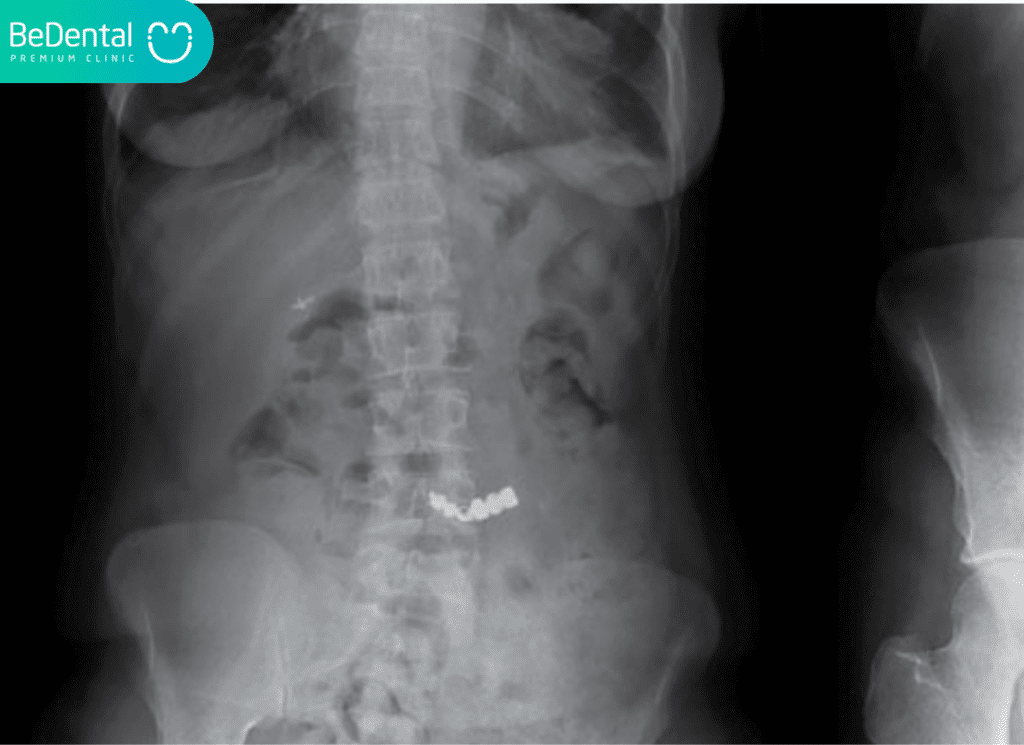

Những dấu hiệu này chứng tỏ chiếc răng đã gây ra những tác động tiêu cực đến cơ thể, có thể là gây thủng niêm mạc hoặc tắc nghẽn đường thở. Khi đó, việc chẩn đoán xem nuốt răng thật vào bụng có sao không sẽ được thực hiện thông qua chụp X-quang để xác định chính xác vị trí của răng trong lồng ngực hoặc ổ bụng, từ đó bác sĩ sẽ có hướng can thiệp nội soi hoặc phẫu thuật kịp thời.

Nếu quá trình theo dõi tại nhà không đem lại kết quả hoặc xuất hiện dấu hiệu đau nhức, bác sĩ sẽ thực hiện một quy trình thăm khám nghiêm ngặt để xác định nuốt răng thật vào bụng có sao không. Chụp X-quang là bước đầu tiên để xác định vị trí hiện tại của chiếc răng. Dựa vào hình ảnh thu được, bác sĩ có thể đánh giá được hình dáng và khả năng gây tắc nghẽn của nó.